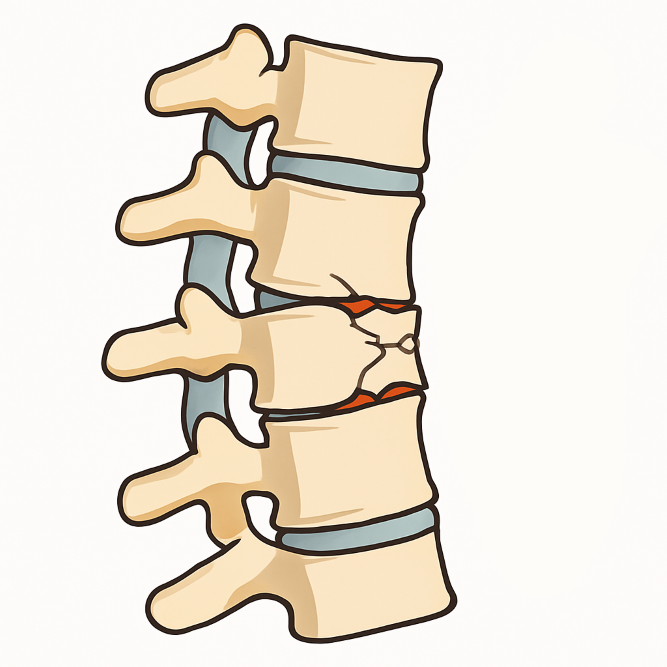

Стабильный перелом позвонка